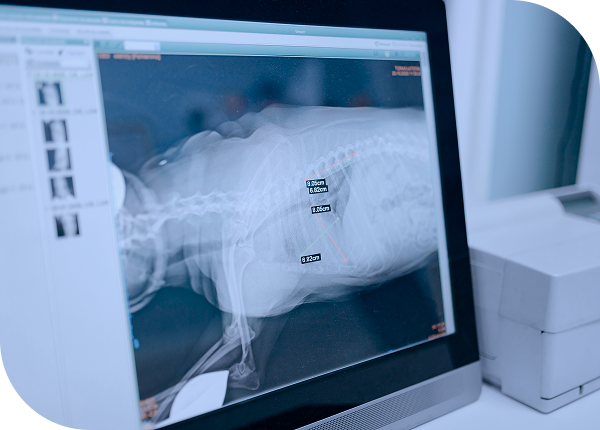

Digital Radiography(DR)는 흉부와 복부 등 전신 구조를 신속하게 확인하는 기본 영상 검사로 다양한 질환을 선별하는 스크리닝 검사로 활용됩니다. Fluoroscopy는 장기의 움직임을 실시간으로 관찰하는 영상 기법으로 식도·기도·요로 등의 기능적 이상을 평가하는 데 중요한 진단 정보를 제공합니다.

빠른 진단 방향 설정

흉부·복부·근골격계를 신속하게 확인해 현재 상태를 파악하고 치료와 추가 검사의 방향을 결정합니다.